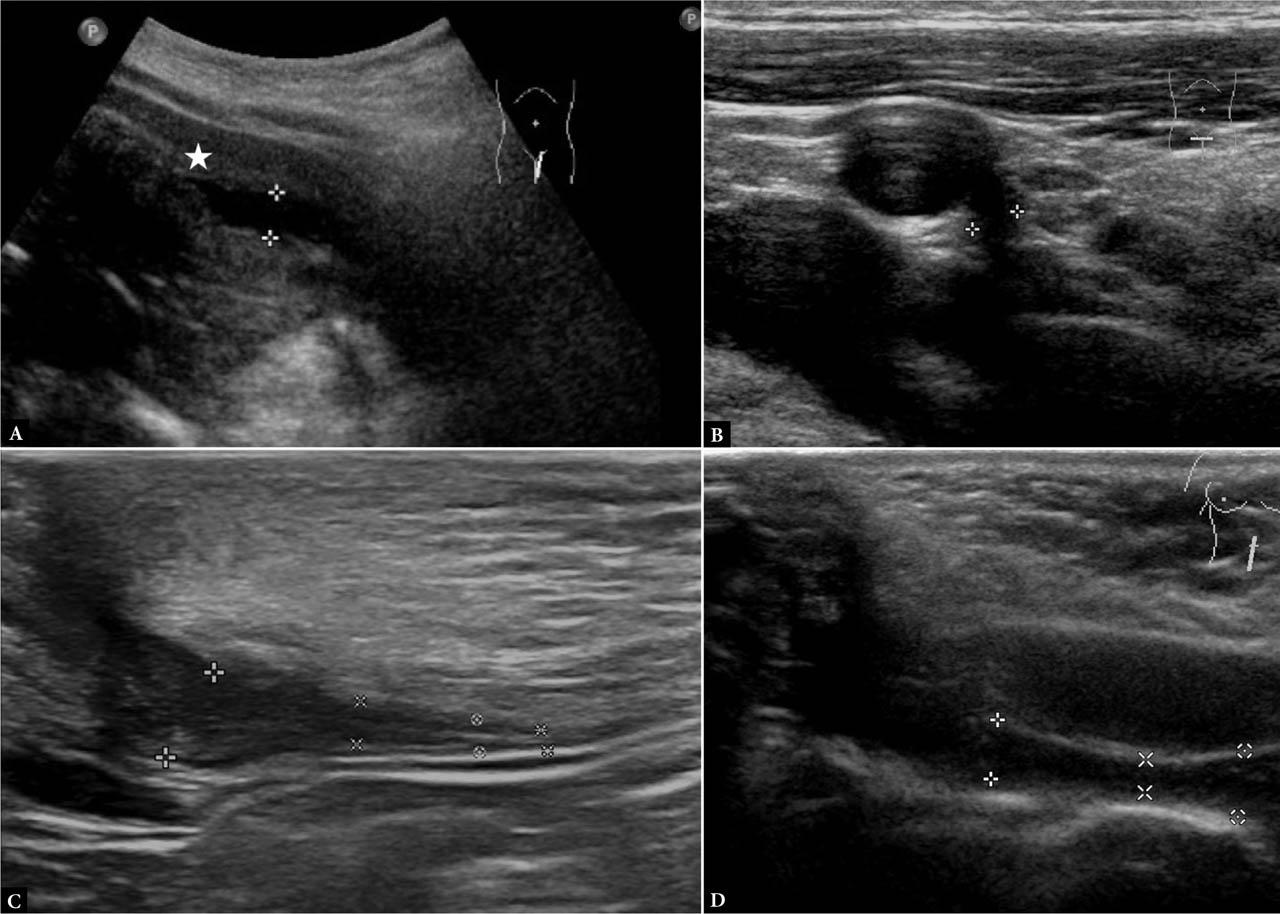

Fig. 1.